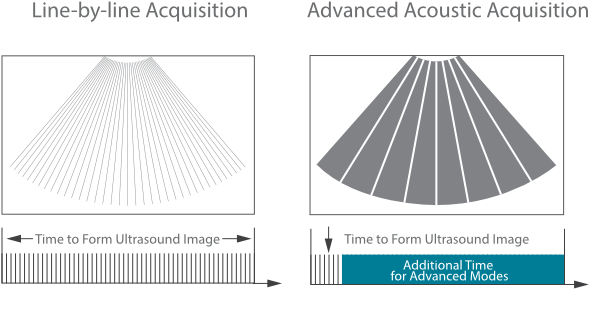

Since the company was founded, Mindray has been continuously exploring new ways to improve diagnostic confidence. Powered by the most revolutionary ZONE Sonography? Technology, Resona 7ŌĆÖs new ZST+ platform brings ultrasound image quality to a higher level by zone acquisition and channel data processing.